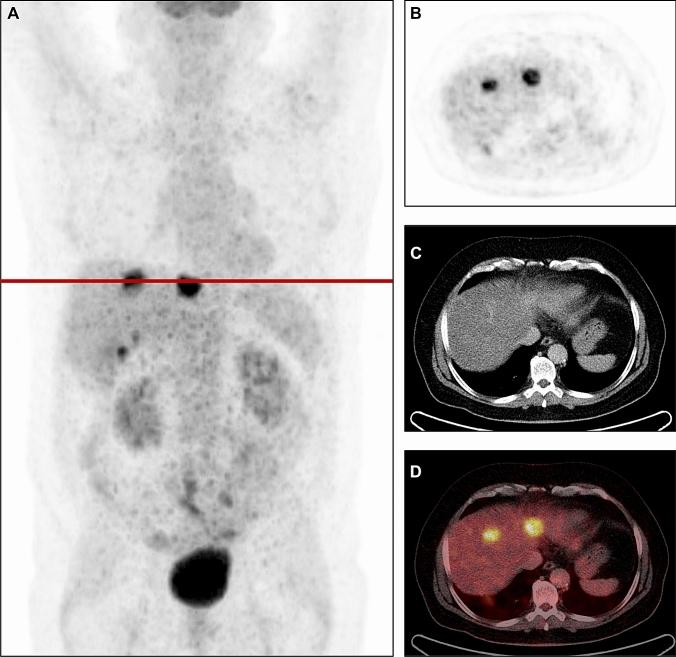

To report 15 years of experience with metabolic tumor volume (MTV) of liver metastases from the preoperative F-FDG PET/CT to predict long-term survival after liver transplantation (LT) for unresectable colorectal liver metastases (CRLM).

The preoperative F-FDG PET/CT from all SECA 1 and 2 patients was evaluated. MTV was obtained from all liver metastases. The patients were divided into one group with low MTV (< 70 cm) and one group with high MTV (> 70 cm) based on a receiver operating characteristic analysis. Overall survival (OS), disease-free survival (DFS) and post recurrence survival (PRS) for patients with low versus high MTV were compared using the Kaplan-Meier method and log rank test. Clinopathological features between the two groups were compared by a nonparametric Mann-Whitney U test for continuous and Fishers exact test for categorical data.

At total of 40 patients were included. Patients with low MTV had significantly longer OS (p < 0.001), DFS (p < 0.001) and PRS (p = 0.006) compared to patients with high values. The patients with high MTV had higher CEA levels, number of liver metastases, size of the largest liver metastasis, N-stage, number of chemotherapy lines and more frequently progression of disease at LT compared to the patients with low MTV.